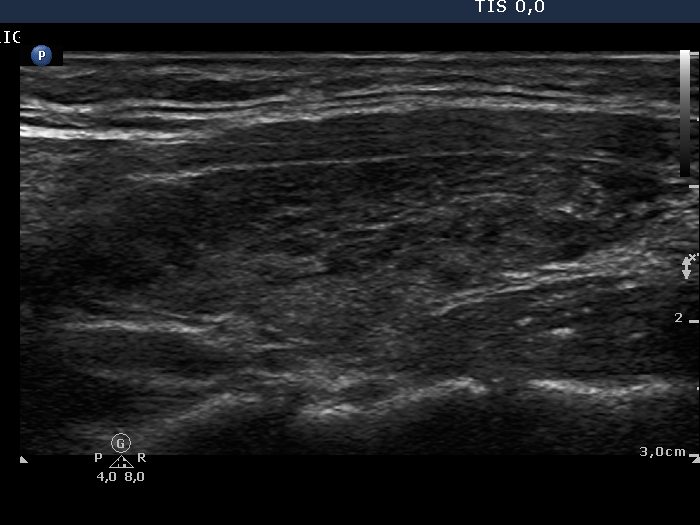

Chronic lymphocytic thyroiditis - Case 2. (ultrasonographic picture 5)

Left lobe, longitudinal view.